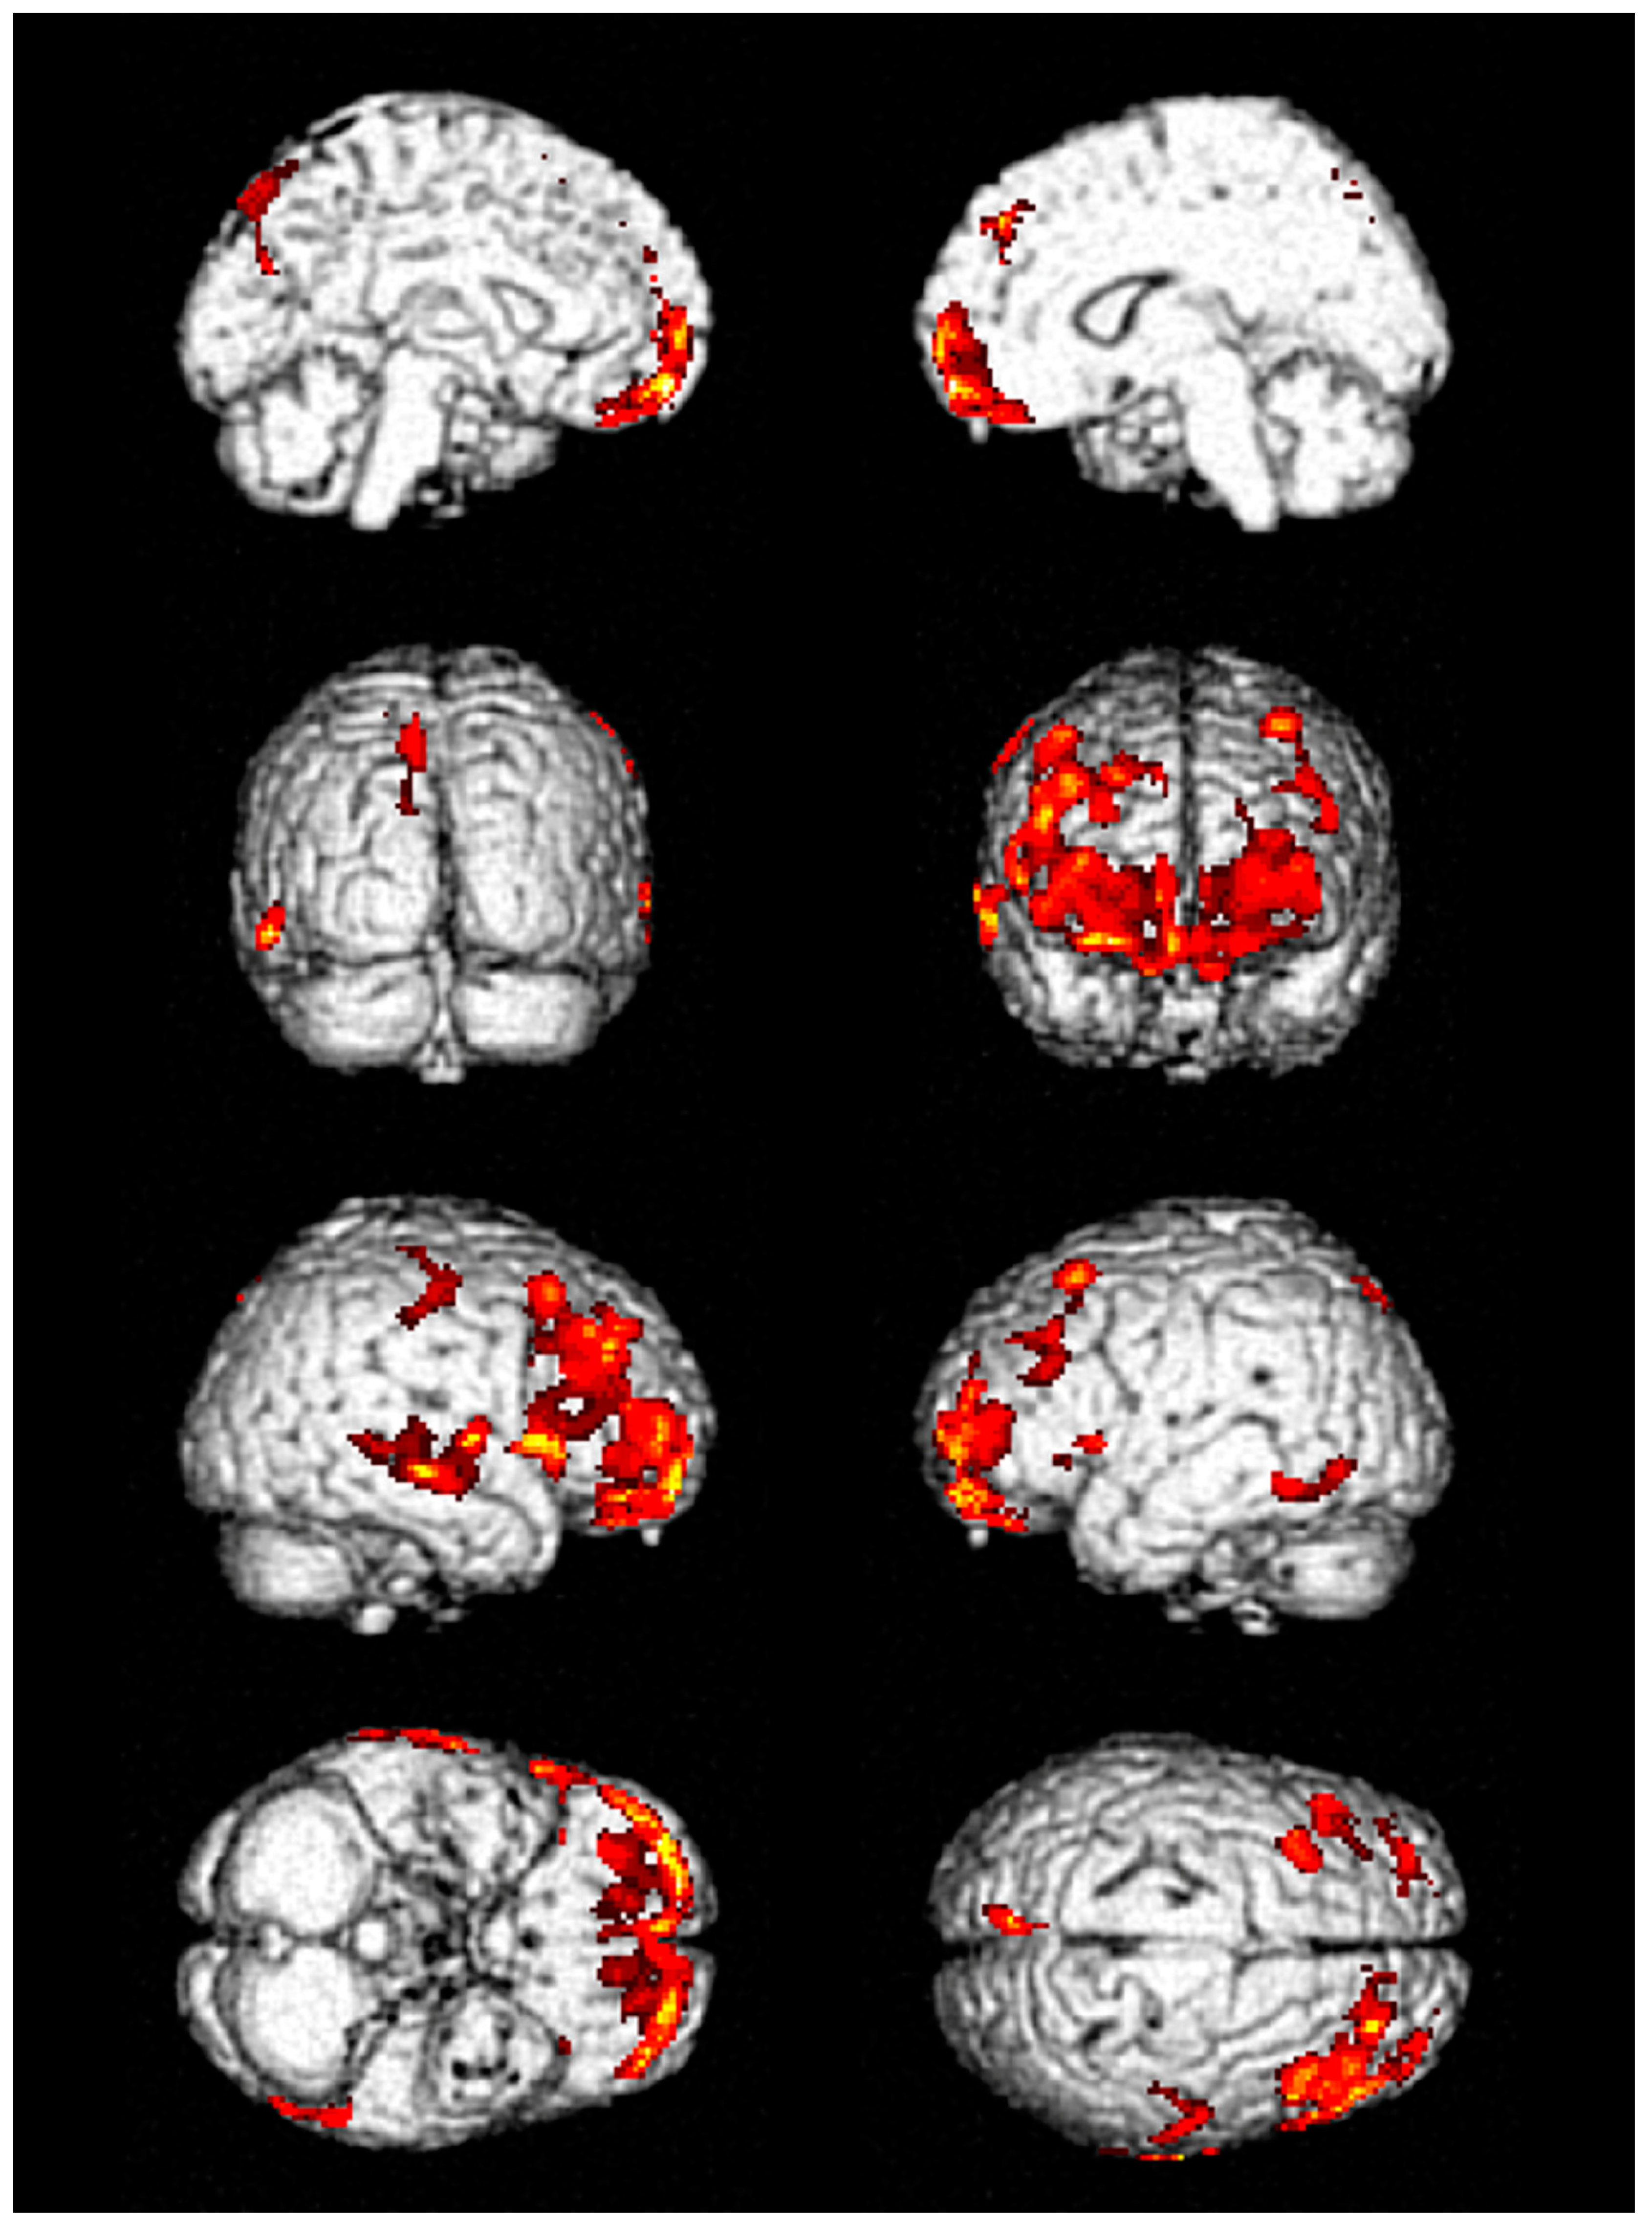

| 1 | Decreased metabolic activity in frontal and temporal lobes | Improved but remained | Improved but remained | 53 | 41 | 6 | 12 |

| 2 | Decreased metabolic activity in frontal and temporal lobes | Improved | Improved | 6 | 3 | No | 3 |

| 3 | Decreased metabolic activity in frontal and temporal lobes | Not performed | Not performed | 14 | 7 | 2 | 6 |

| 4 | Decreased metabolic activity in inferior frontal lobe | Not performed | Not performed | 10 | 6 | 1 | 1 |

| 5 | Decreased metabolic activity in frontal lobe | Not performed | Not performed | 12 | 4 | 1 | 1 |

| 6 | Decreased metabolic activity in frontal and temporal lobes | Not performed | Not performed | 24 | 8 | 3 | 2 |

| 7 | Decreased metabolic activity in frontal and temporal lobes | Not performed | Not performed | 19 | 13 | 3 | 1 |

| 8 | Decreased metabolic activity in frontal and temporal lobes | Improved | Not performed | 9 | 3 | No | 2 |

| 9 | Decreased metabolic activity in frontal and temporal lobes | Not performed | Not performed | 11 | 5 | 2 | Loss |